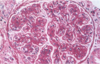

What type of antibody associated injury could be pictured?

The image has a Granular appearance indicating the antibody associated damage could be a number of things including deposition of circulating complexes or in-situ complexes anywhere except in the BM.